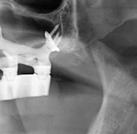

Exploración radiológica

Mediante CBCT constatamos atrofias óseas severas y disminución de soporte óseo periodontal en relación con las piezas dentales.

procediendo a realizar una solicitud de encargo a través de un formulario. Antes de 72 horas recibimos una propuesta terapéutica. En ella se facilitan vistas 3D detalladas, así como valoraciones y consideraciones a tener en cuenta durante el fresado y la inserción de los implantes (Figuras 9 a 19). Decidimos realizar extracción de todas las piezas remanentes, dada su nula viabilidad a corto-medio plazo y en Bego (a través del portal) proponen mantener 3 piezas (las más viables técnicamente) en cada arcada para proporcionar el anclaje óptimo de la

Figura 10. Propuesta de planificación maxilar con encerado diagnóstico digital. Destaca la angulación del implante 1.6 esquivando el seno maxilar con un ángulo de inserción de 30 º y una emergencia protésica verticalizada.

16. Superposición radiológica implante 45 angulado, teniendo en consideración el encerado diagnóstico y preservando estructuras nerviosas.

Figura 14. Representación tridimensional. Destaca la protección de estructuras nobles (nervio mentoniano) al presentar un implante angulado con íntima relación.

Figura 15. Visión general tridimensional. Destaca la uniformidad en la disposición de los implantes. En amarillo emergencia implantológica y en gris emergencia protésica mediante pilares transepiteliales angulados multiplus.